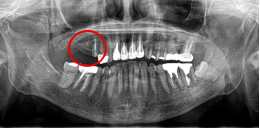

男性 Eさん 80代 (インプラント)

主訴

左上2本が動いていて、噛むと痛みがある。歯がないところに歯を入れたい。

治療内容

左上第二小臼歯と第一大臼歯の歯根が破折していたため、保存することができず抜歯しました。第一小臼歯は、すでにありませんでしたので、2本抜歯後3本欠損のところにインプラントを2本埋入しました。

所感

2006年10月に右下と左下の欠損部分にインプラント治療をしました。今回も左上の歯を失ったところは、インプラント治療を希望されました。

インプラント2本:¥363,000✕2本=¥726,000(税込)

ポンティック1本:¥115,500(税込)

合計:¥841,500(税込)

Before

※赤丸は、歯根が破折していたため抜歯しました

※黄色丸は、2006年10月に埋入したインプラント

After

※緑丸は、今回埋入したインプラント